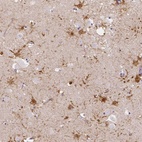

Immunohistochemical staining of human caudate shows strong cytoplasmic and nuclear positivity in astrocytes.